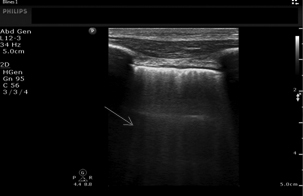

Lung ultrasound (US) has many benefits because it is a low-cost, rapid, bedside assessment tool, and it is performed without exposure to ionizing radiation.47,48 The presence of B-lines seen on bedside ultrasound is predictive of an acute HF presentation.47 (See Figure 2.) The differential diagnosis for the presence of diffuse B-lines on lung US includes interstitial edema (both cardiogenic and noncardiogenic), acute respiratory distress syndrome (ARDS), interstitial pneumonia, and parenchymal lung disease (e.g., pulmonary fibrosis).49 Unilateral or localized pathologic B-lines suggest a localized process such as pneumonia.46

Figure 2. B Lines (arrow) on Lung Ultrasound |

Source: Image used with permission from Daniel Haase, MD, RDCS, RDMS. |

Comparison studies have shown that lung US is more accurate than CXR in diagnosing pulmonary edema.50 In a 2018 systematic review by McGivery et al, the pooled sensitivity and specificity of lung US for the diagnosis of acute HF was 82.5% and 83.6%, respectively.51 A 2019 study by Pivetta et al found that lung US was more accurate than the combination of clinical examination, CXR, and natriuretic peptides.52 They also found that the use of lung US reduced diagnostic errors and reduced the median time for diagnosis from 104.5 minutes to five minutes.52 Another study by Maw et al in 2021 found that the sensitivity of lung US (88%) was superior to CXR (73%), while the specificity remained consistent (90% for both lung US and CXR).48

There are potential limitations to the use of lung US, including inter-provider reliability and specificity of findings.53 Use of lung US has a level B recommendation (reflects moderate scientific certainty) by the American College of Emergency Physicians (ACEP) in conjunction with medical history and physical examination for undifferentiated dyspneic patients with concern for acute heart failure who present to the ED.47